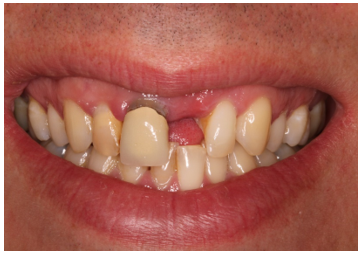

• Has a UL1 denture and hates it

• Does not like the margin on the UR1

Before And After

The patient has a high lip line and aesthetic outcome was important